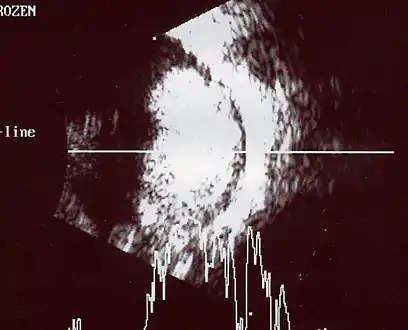

If the eye examination is abnormal, further testing may include imaging studies, such as computerized tomography (CT), magnetic resonance imaging (MRI), and ultrasound.[28] CT and MRI can help define the structure abnormalities and reveal any calcium depositions. Ultrasound can help define the height and thickness of the tumor. Bone marrow examination or lumbar puncture may also be done to determine any metastases to bones or the brain.

Aspect of trilateral retinoblastoma on MRI An ocular ultrasound of a large retinoblastoma tumor within the eye of a 3-year-old boy

Traditional ultrasound B scan can detect calcifications in the tumour while high-frequency ultrasound B scan is able to provide higher resolution than the traditional ultrasound and determine the proximity of the tumour with front portion of the eye. MRI scan can detect high-risk features such as optic nerve invasion; choroidal invasion, scleral invasion, and intracranial invasion. CT scan is generally avoided because radiation can stimulate the formation of more eye tumours in those with RB1 genetic mutation.[35]